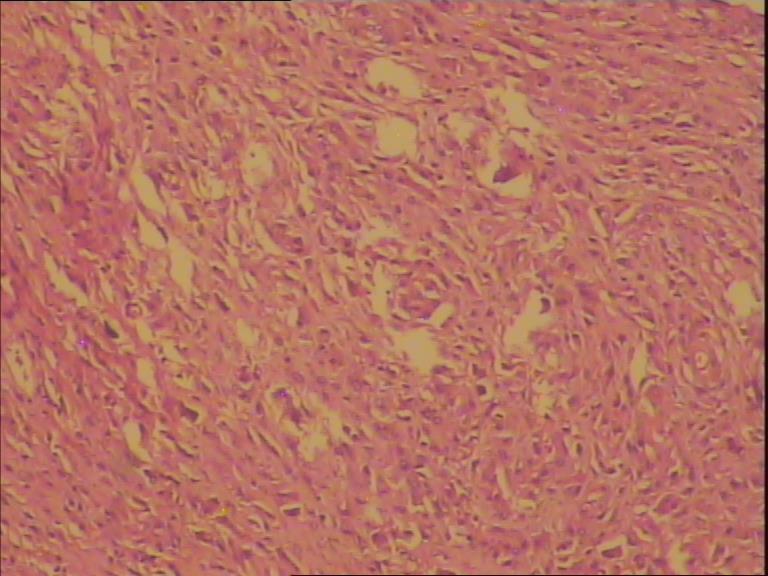

骨巨细胞瘤1级

膝关节置换术后7年,疼痛6月。 术中见关节假体周围大量增生肉样、葡萄状组织。是否有骨质浸润手术医生说不清楚,X片未见骨质浸润。

膝关节腔内肿物

灰白组织一堆直径7cm,部份组织呈葡萄样。

那些颗粒状物是假体脱下来的碎屑,巨细胞首先考虑是反应性的。

会诊意见:见大量组织细胞,多核j巨细胞反应,未见明确肿瘤性病变。